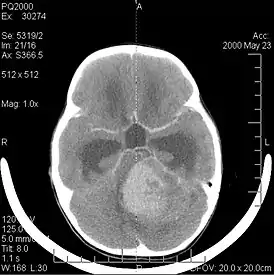

Компьютерная томография

В типичных случаях на КТ медуллобластомы определяются как объёмные образования круглой или овальной формы, которые неоднородно накапливают контрастное вещество и располагаются в проекции червя мозжечка. Данные новообразования смещают IV желудочек вентрально. Достаточно часто определяются кисты (до 65 %) и микрокальцинаты[20].